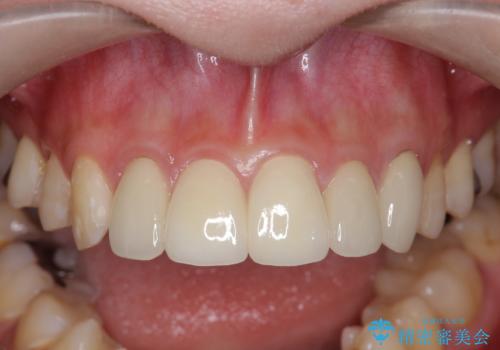

不適合なクラウンのやりかえ

- 数ヶ月前に他院で装着したセラミッククラウンから、歯ブラシのたびに出血することの改善を求めて来院されました。

X線写真よりクラウンの際があっていない状態であることがわかり、再度精度の良いセラミッククラウンを製作していくこととなりました。

- 22万円(仮歯・ジルコニアクラウン×2)費用は治療当時の料金となります

残存している歯と、クラウンの合いが悪い(不適合クラウン)歯汚れは溜まりやすく歯ぐきが腫れ虫歯・歯周病の再発リスクを高めます.